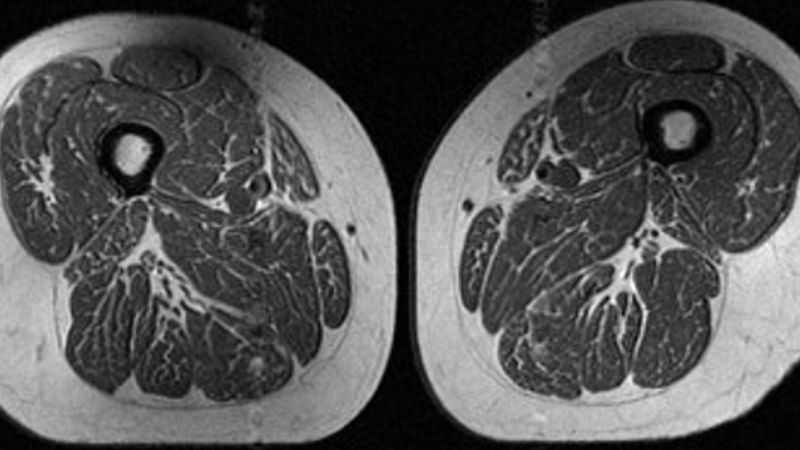

The picture appears to be like like a slice of extremely marbled flesh, paying homage to a high-end steak with considerable fine-grained streaks of fats. But that’s not dinner. It’s an MRI scan of the thigh of a 62-year-old girl who obtained 87% of her annual energy from ultraprocessed food.

A 61-year-old girl within the study additionally had fats marbling in her thigh muscles, however it was not as intense. About 29% of her annual weight loss program consisted of ultraprocessed foods.

The 61-year-old girl with a weight loss program consisting of 29.5% ultraprocessed meals (A in picture beneath) had a barely increased BMI of 32.6 and a a lot decrease exercise rating than the lady (B in picture) with a BMI of 31.8 whose weight loss program was 87.1% ultraprocessed. Yet the lady with the upper ultraprocessed rating nonetheless had dramatically extra fats marbling in her thighs.